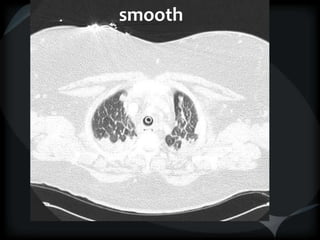

Septal Pattern – lymphatic/venous

 Secondary lobule outlined- interlobular septum

● Smooth – pulmonary veno-occlusive disease, mitral

stenosis, capillary hemangiomatosis, LC

● Beaded – lymphangitic carcinomatosis, lymphoma,

lymphangiomatosis, sarcoid

Rare = non-Langerhans’ cell histiocytosis (bone+pleura)

amyloidosis

smooth

LC

beaded